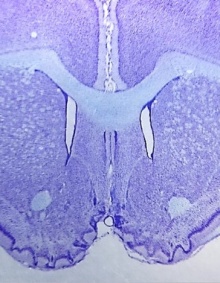

Thionin-stained coronal section of a rodent brain, from the Neurobiology of Habitual Behaviors Laboratory